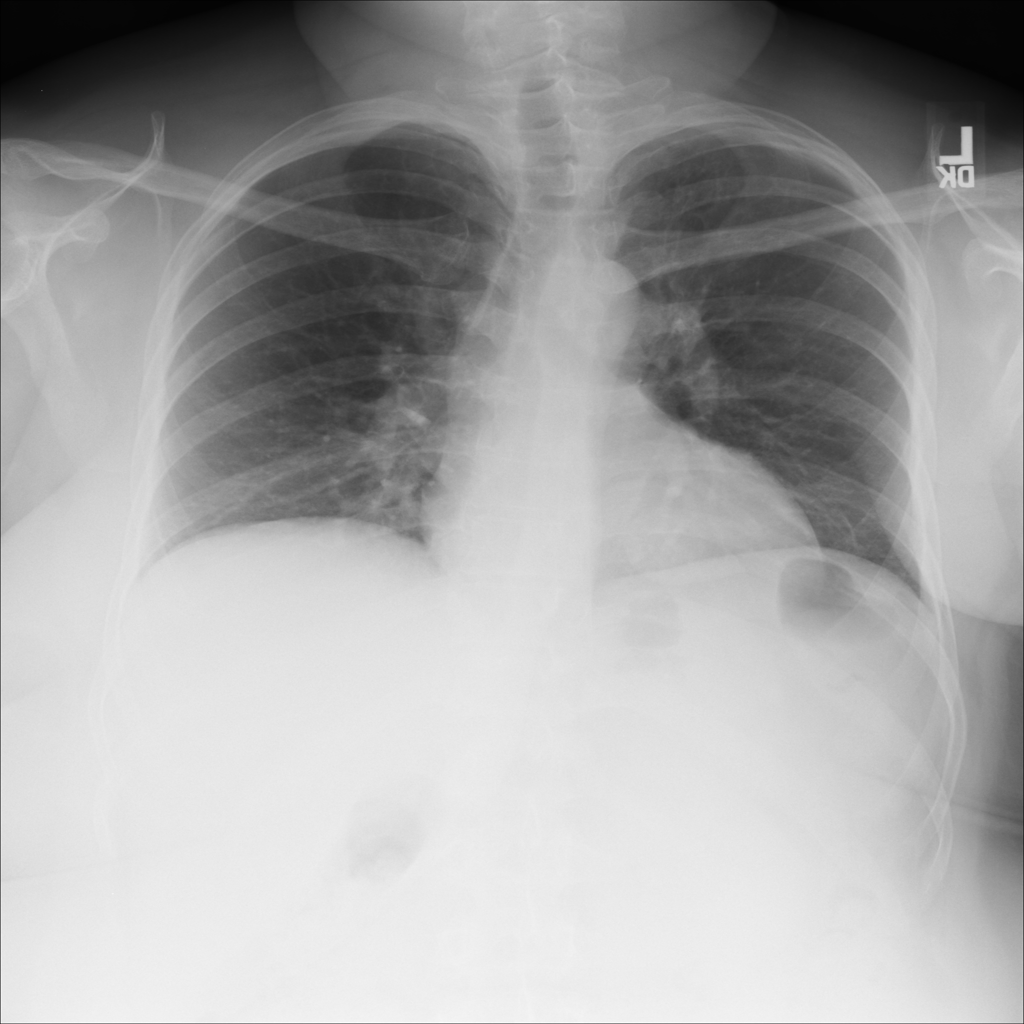

PAT-1F50 · IMG-000Fibrosis

PAT-1F50 · IMG-000

PA